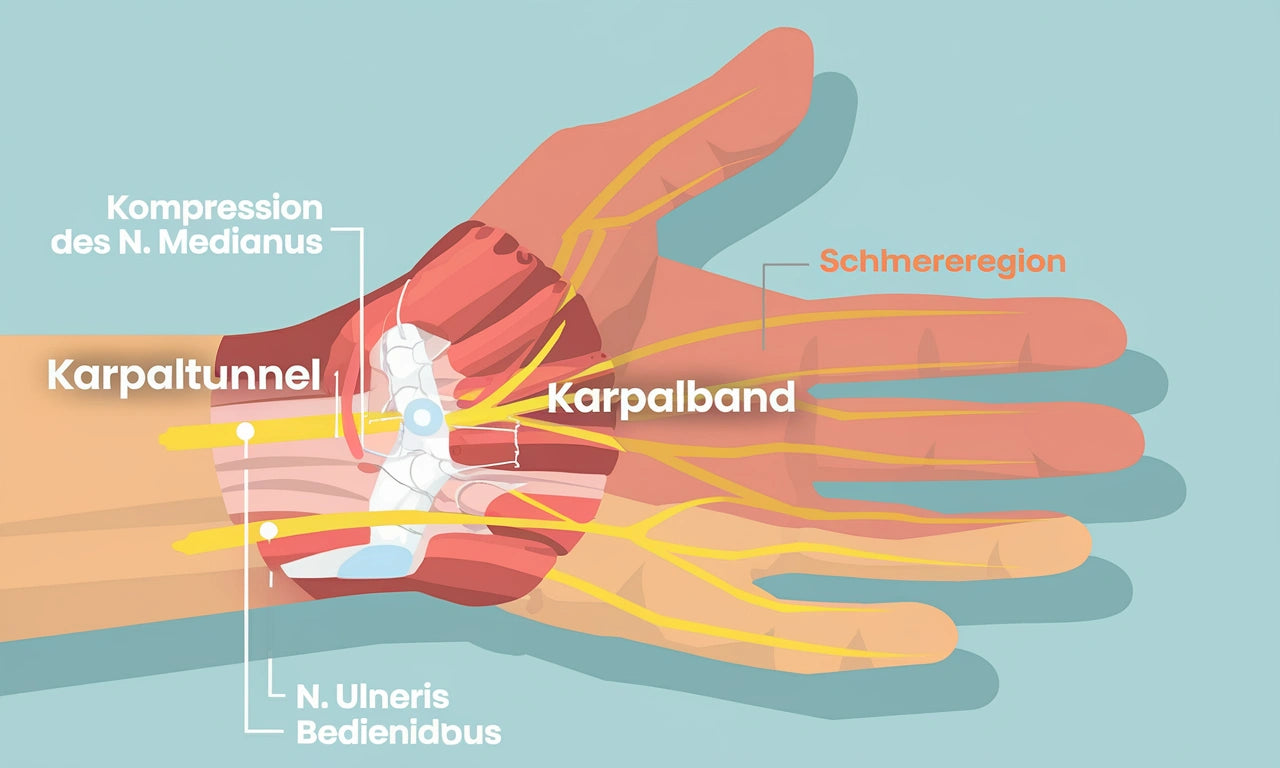

Händerna används hela tiden, så när smärta eller domningar uppstår kan det bli mycket begränsande. Oavsett om det handlar om karpaltunnelsyndrom, reumatism eller stickningar i fingrarna hjälper vi dig att förstå orsakerna och möjliga lösningar.